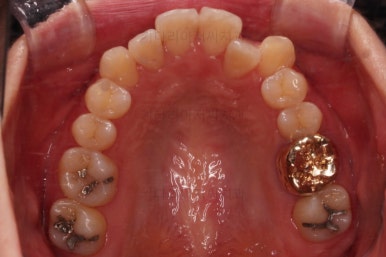

초진 시, 입안의 모습입니다.

좌측 송곳니가 덧니처럼 튀어나가 있고, 송곳니 옆의 작은 억므니가 안으로 쏙 들어가서 덧니 느낌이 더 강조되어 보이네요.

위아래 앞니가 긴밀하게 겹침이 없는 약간의 개방교합(오픈바이트, Openbite) 경향이 보입니다.

이번 환자분도 삐뚤한 치열을 비발치로,심지어 미니스크류 사용도 없었고 치간삭제도 거의 하지 않았는데요.